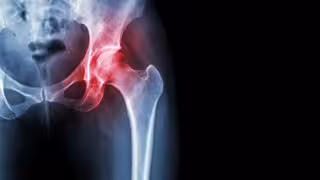

Archivo - Necrosis avascular de cadera

Archivo - Necrosis avascular de cadera - HOSPITAL LA LUZ - Archivo

Aproximadamente uno de cada seis pacientes mayores de 70 años ha sufrido alguna fractura de fragilidad y, de ellos, más de un tercio sufrirá nuevas fracturas. La fractura de cadera es la que mayor mortalidad, dependencia y gasto sanitario conlleva, con solo uno de cada cuatro pacientes recuperando la autonomía previa a la fractura.